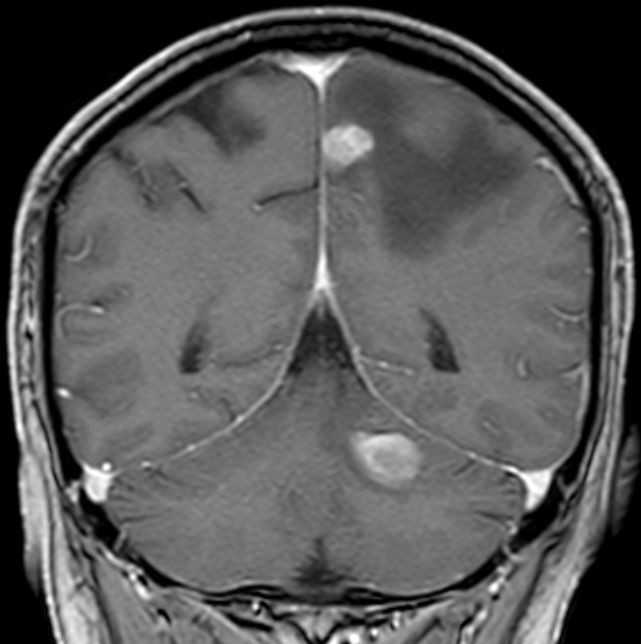

| Hirnmetastasen. Fallbeispiel späte multiple Fernmetastasen nach regionalem Rezidiv | 86-jähriger Mann, der vor 7 Jahren ein Melanom der rechten Schulter hatte.

Vor 6 Monaten axilläres Rezidiv, Exzision, Strahlentherapie. Jetzt Hirnmetastasen, Lungen- und Lebermetastasen.![]() | |||